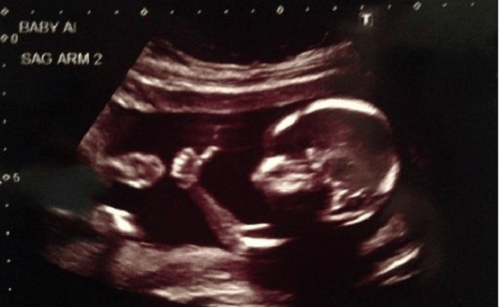

The Supreme Court has declined to take up a challenge to Kentucky’s law requiring abortion center staff to show each patient her ultrasound images and describe the dimensions of her unborn baby and the presence of internal organs, if seen.

The lone abortion clinic in Kentucky routinely performs ultrasounds before doing abortions, but doesn’t like patients to see the images, since so many women change their minds after seeing they are carrying a baby, not a blob.